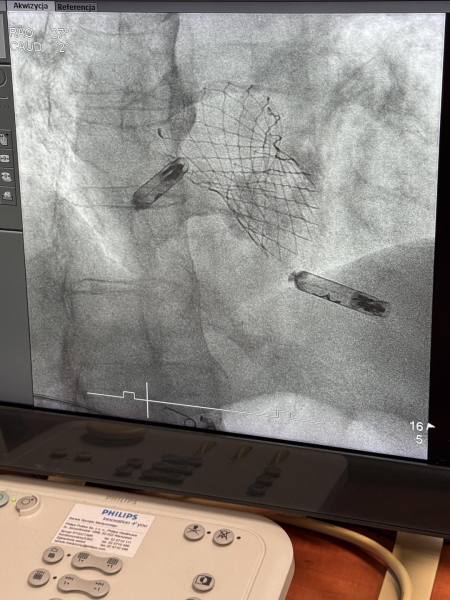

Lekarze z rzeszowskiego wykonali pierwszy w Polsce zabieg wszczepienia podwójnego rozrusznika serca bez przewodów. 77-letni pacjent otrzymał urządzenie, którego części rozmawiają ze sobą przez Bluetooth. Zabieg przeprowadzono wczoraj w szpitalu wojewódzkim.

Rzeszowscy kardiolodzy dokonali przełomu w polskiej medycynie. Po raz pierwszy w kraju wszczepili pacjentowi podwójny system stymulujący serce bez tradycyjnych przewodów.

Jedna część urządzenia została umieszczona w prawym przedsionku, druga w prawej komorze serca. Obie części rozmawiają ze sobą i wspólnie pilnują rytmu serca. Pacjent miał problemy zdrowotne, które uniemożliwiały wszczepienie zwykłego rozrusznika.

Wcześniej rozruszniki wszczepiano tylko w jedno miejsce – przedsionek albo komorę. Teraz po raz pierwszy udało się wszczepić oba elementy jednocześnie.